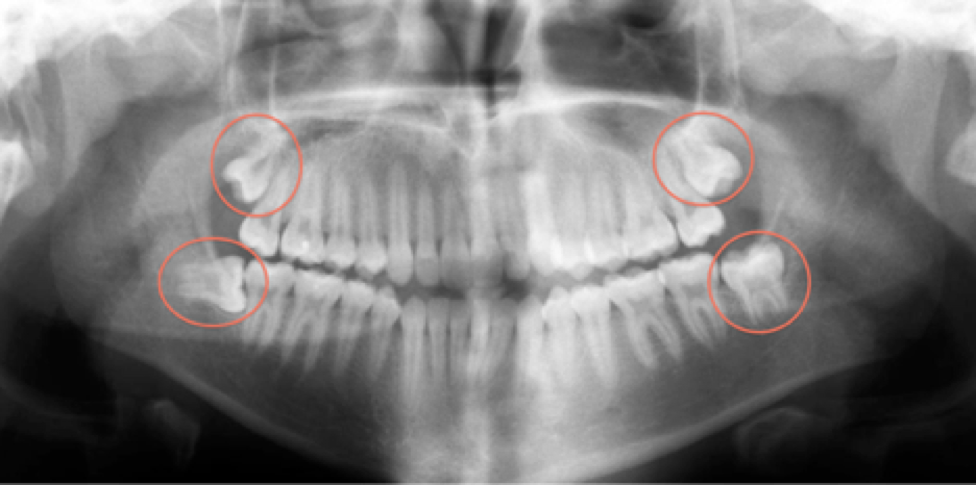

Wisdom teeth, or third molars, typically appear in your late teens or early twenties. However, these late bloomers often cause more trouble than they’re worth. An impacted wisdom tooth can cause severe pain and complications, necessitating removal.

If wisdom teeth are growing in properly and don’t cause any pain, they can usually stay put. However, wisdom tooth removal becomes necessary when people experience one or more of the following issues:

- Impaction: The teeth are trapped in the jawbone or gums and don’t break through the surface properly.

- Misalignment: The teeth grow at odd angles, potentially damaging adjacent teeth.

- Overcrowding: There simply isn’t enough room in the mouth for these extra teeth.

Take it from Dr. Smith, a renowned oral surgeon: “Impacted wisdom teeth can lead to severe pain, infections, and even damage to neighbouring teeth. Removing them is often a necessity to prevent these complications.” Tooth removal is often necessary to prevent complications from impacted wisdom teeth.